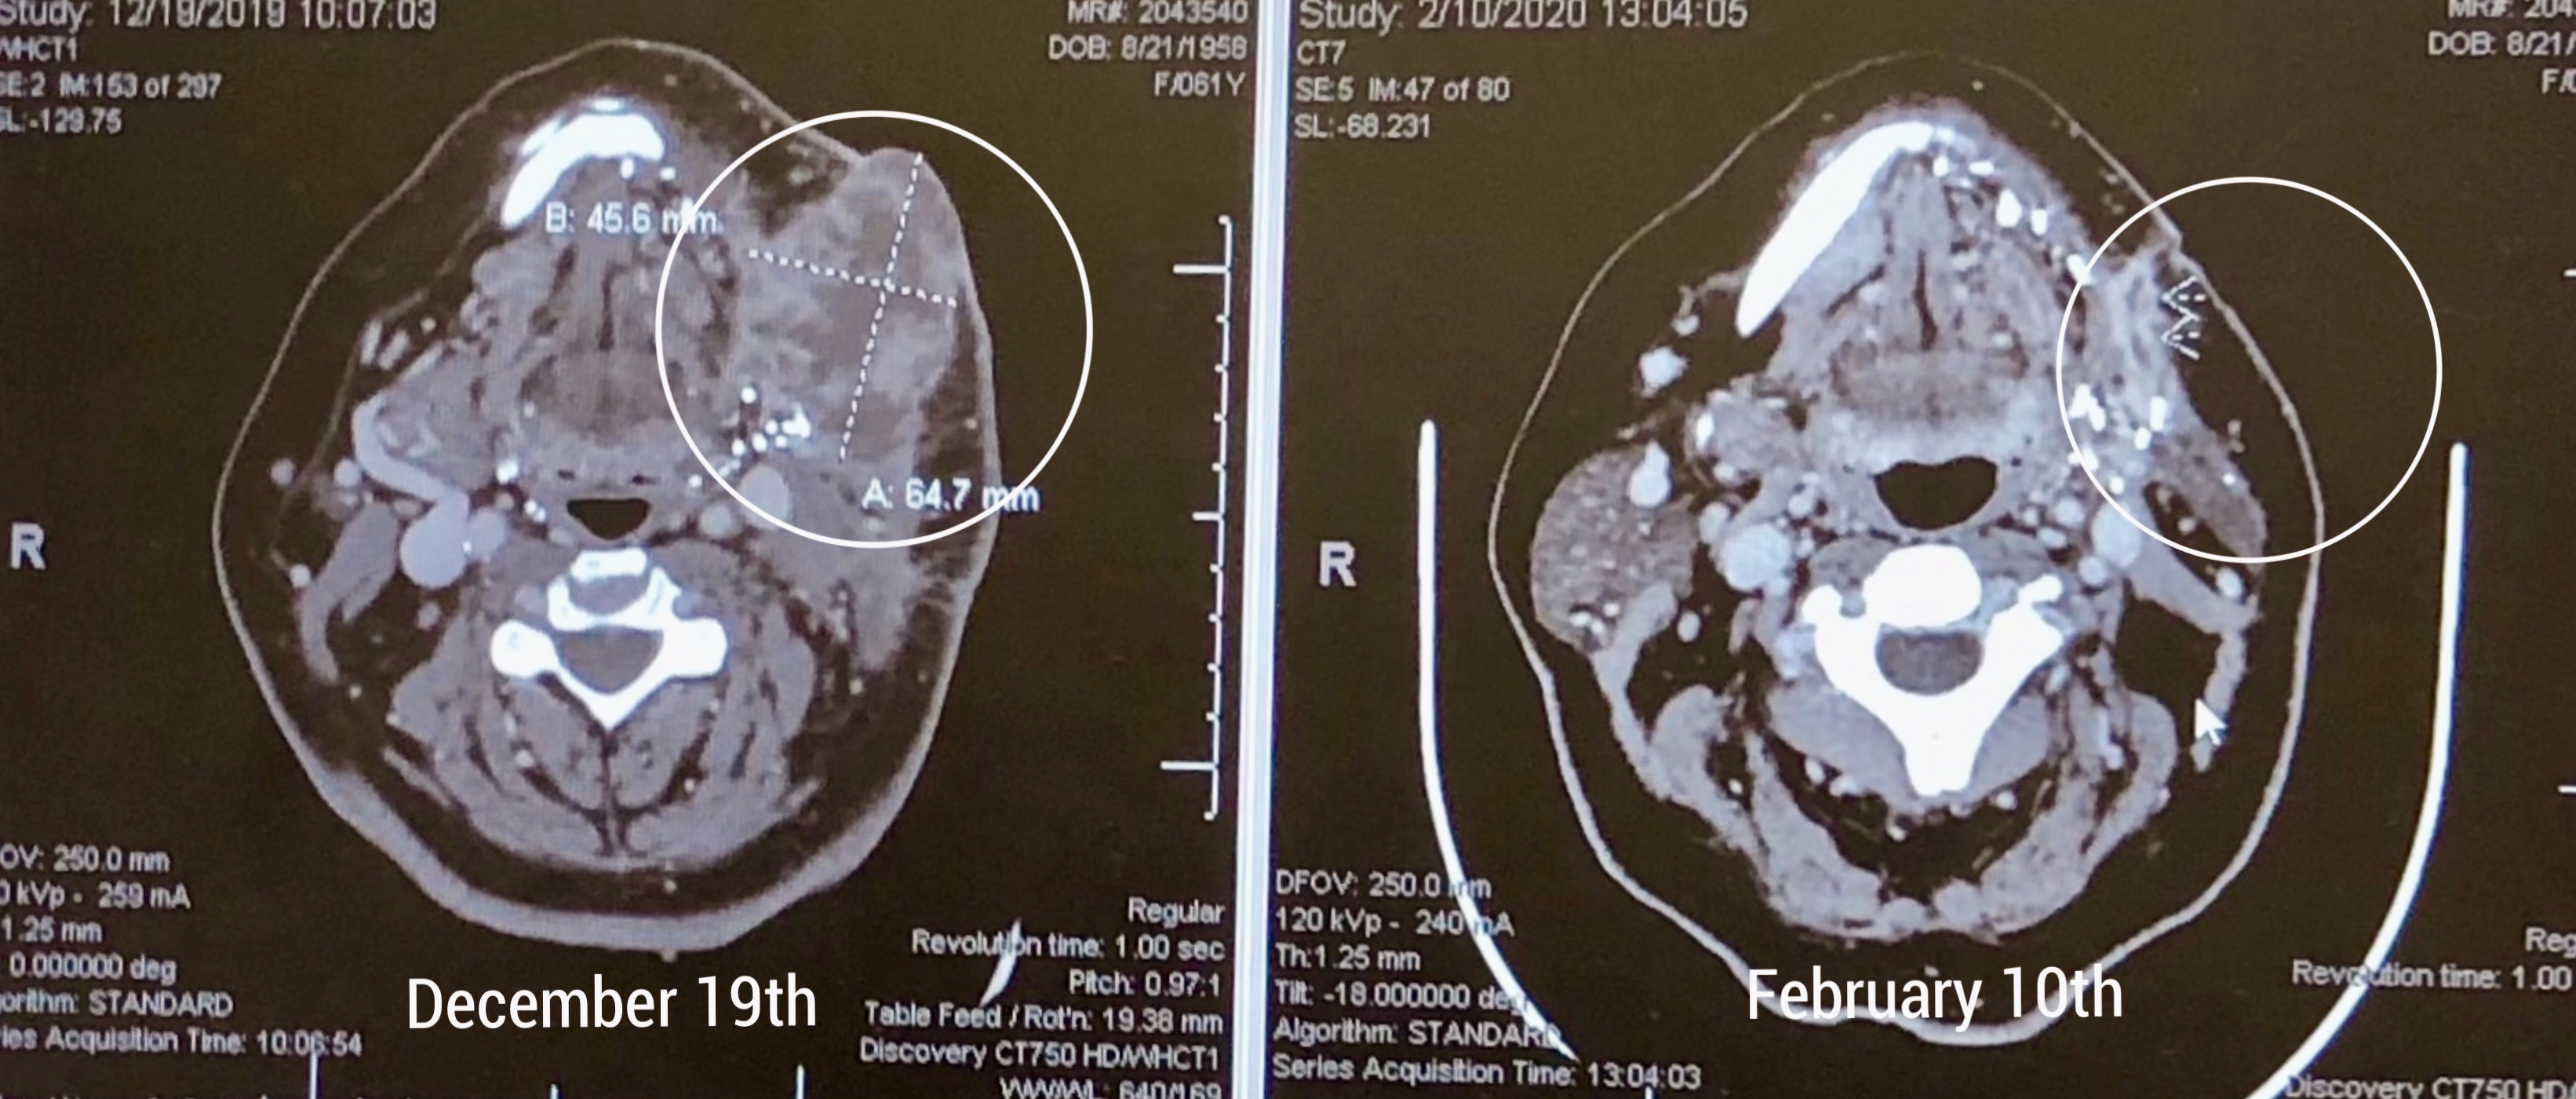

More CT Scans - February 10th 2020

Since Rob was here for a visit this week, we thought we would treat him to a day at MD Anderson downtown! Although we are not, by any means, out of the woods, we received some encouraging news. Christine had another CT scan today, and scan images (on web page), shows the tumor that was identified on December 19th, has considerably reduced in size after the two rounds of chemotherapy. Dr. Blumenschein was absolutely gobsmacked with these results. Christine will be having a third round of chemotherapy on Wednesday, after which the remaining tumor will be surgically removed on March 13th. We both thank you all very much for your continual support and good wishes. Christine will likely be out of action from Saturday for five or six days due to the fatigue caused by the chemotherapy treatment.